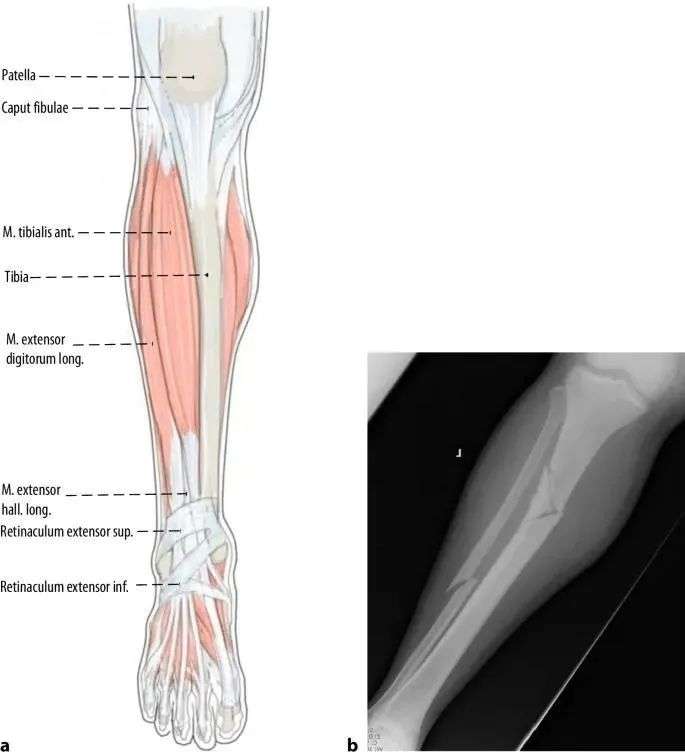

Anu ngabalukarkeun utama malalignment dina fractures tibial proksimal nyaéta deformity disababkeun ku narik tina urat quadriceps salila flexion dengkul jeung konflik mékanis antara ujung kuku jeung cortex tibial posterior salila sisipan susuk. Patella ogé nyegah asupna axial tina paku dina pesawat sagittal (Gbr. 1a, b). Ku alatan éta, métode umum sejen nuliskeun titik ngaliwatan incision parapatellar medial, nu ngakibatkeun sisipan kuku rada medial-to-lateral (Gbr. 1c jeung 2). Nalika kuku asup kana kanal intramedullary distal ka narekahan, bagian proksimal dimiringkeun kana hiji exostosis (Gbr. 2). Tungtungna, tegangan istirahat tina otot chamber anterior nyumbang rada ka ectropion nu (Gbr. 3).

Gambar 1 a,b Ngagunakeun pendekatan infrapatellar konvensional, patella nu nyegah asupna axial tina paku, hasilna deformity umum anterior apical alignment sagittal na ectropion coronal alignment.c Intramedullary alignment kuku dipigawé ngagunakeun pendekatan parapatellar.